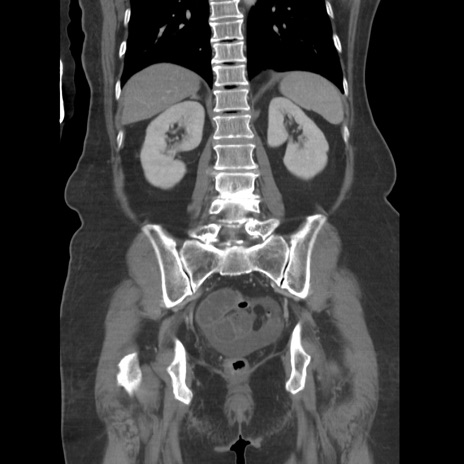

症例19(冠状断像)

【症例】80歳代女性

【主訴】下腹部痛

【現病歴】約8時間前より下腹部痛の出現あり、救急外来受診。

【既往歴】両側付属器切除

【身体所見】意識清明、下腹部正中に手術痕あり、その部位に一致して圧痛と反跳痛あり。腸蠕動音は亢進。

【データ】WBC 9300、CRP 0.15